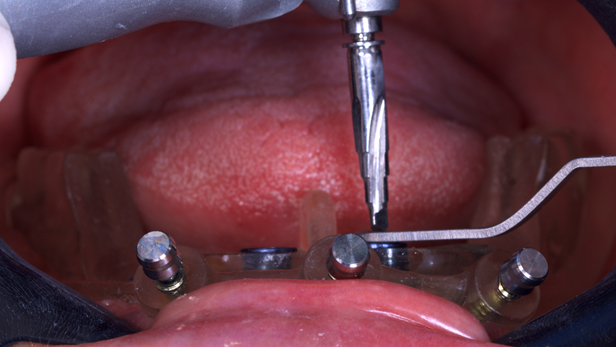

A cirurgia guiada para colocação dos implantes foi realizada em clínica odontológica sob anestesia local, Cloridrato de Mepivacaína 2% com adrenalina. Anteriormente, a guia era testada na boca para verificar o encaixe perfeito.

O guia foi fixado após estabilização em oclusão com a prótese superior. Após a retirada do guia de oclusão, foi fixada a guia de fresagem e instalação dos implantes, que foram instalados com torques superiores a 32N, o que permitiu a captura imediata da prótese provisória através do pilar de titânio e resina de fluxo.